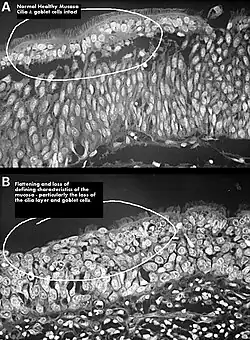

One possible cause may be changes to the nasal mucous membrane and to the nerve endings in the mucosa resulting from chronic changes to the temperature and humidity of the air flowing inside the nose, caused in turn by removal or reduction of the turbinates.[3][7] The TRPM8 receptor, responsible for the sensation of nasal openness (patency), is activated by high-speed airflow, which cools the nasal lining through evaporation. This cooling triggers signals to the brain, making breathing feel easier. Nasal passage enlargement alters airflow, reducing turbulence and mucosal cooling which results in reduced sensation of airflow. Studies confirm that without the inferior turbinate, air conditioning in the nose is less effective.[7]

.jpg)

It has been proposed, that the airflow in ENS is changed so that most of the air flows through the middle meatus, compared to most of the air flowing through the inferior meatus in healthy individuals. This can be corrected via inferior meatus augmentation (IMAP surgery).[25]